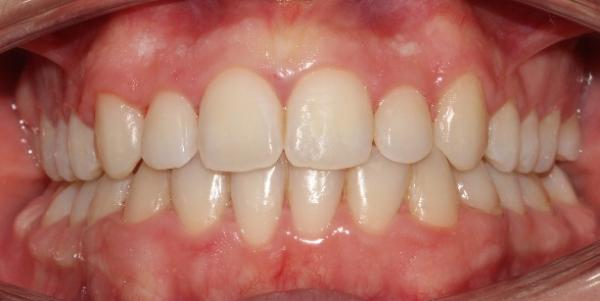

The patient in this case is a 15-year-old female who presented with mild third skeletal class with upper and lower tooth crowding at the beginning of the treatment. The whole process lasted for around 20 months employing traditional metal brackets.

Fig 1,2,3: the intraoral condition before orthodontics treatment & Fig 4,5,6: the intraoral condition after orthodontics treatment.